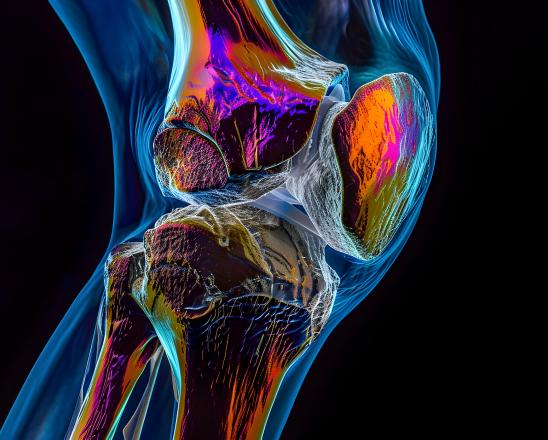

Well, take a look at this picture:

This is the most dangerous acid in the world.

It’s called “fluoroantimonic acid” and it can burn through almost anything including glass, ceramic materials, and even some metals.

And as scary as this may sound, YOU actually have a similar acid building up and bubbling inside your joints…

And when this acid builds up…

It eats away at your joints just like that acid eating through sheet metal…

And over time this literally works to DISSOLVE the cartilage and other cushioning tissues from the inside out.

As a result, your joints suffer and you experience aches, stiffness, and burning…